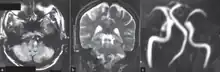

-

a)High signal in left postero lateral indicates a infarct and thrombosed left vertebral artery b) infarct (circle ) c)indicates absence of normal left vertebral artery ( circle ) -

Clinical B1000 diffusion weighted MRI image showing an acute left sided dorsal lateral medullary infarct -